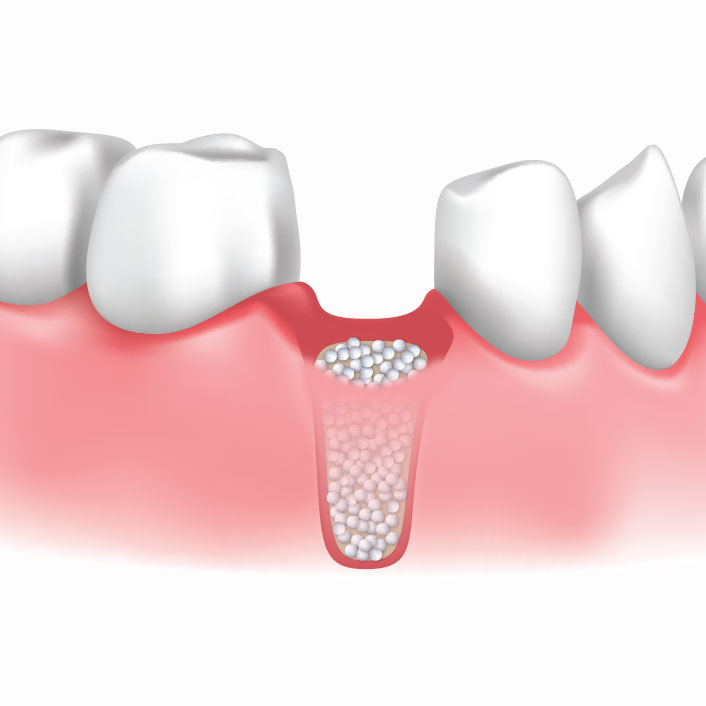

Bone grafting is a procedure used to rebuild and strengthen the jawbone when there is not enough bone to support a dental implant. This is often needed after tooth loss or gum disease, which can cause the bone to shrink over time.

A bone graft helps restore volume and density to the area, creating a strong foundation for future implant placement. In some cases, a sinus lift may also be performed in the upper jaw to create additional space and support.